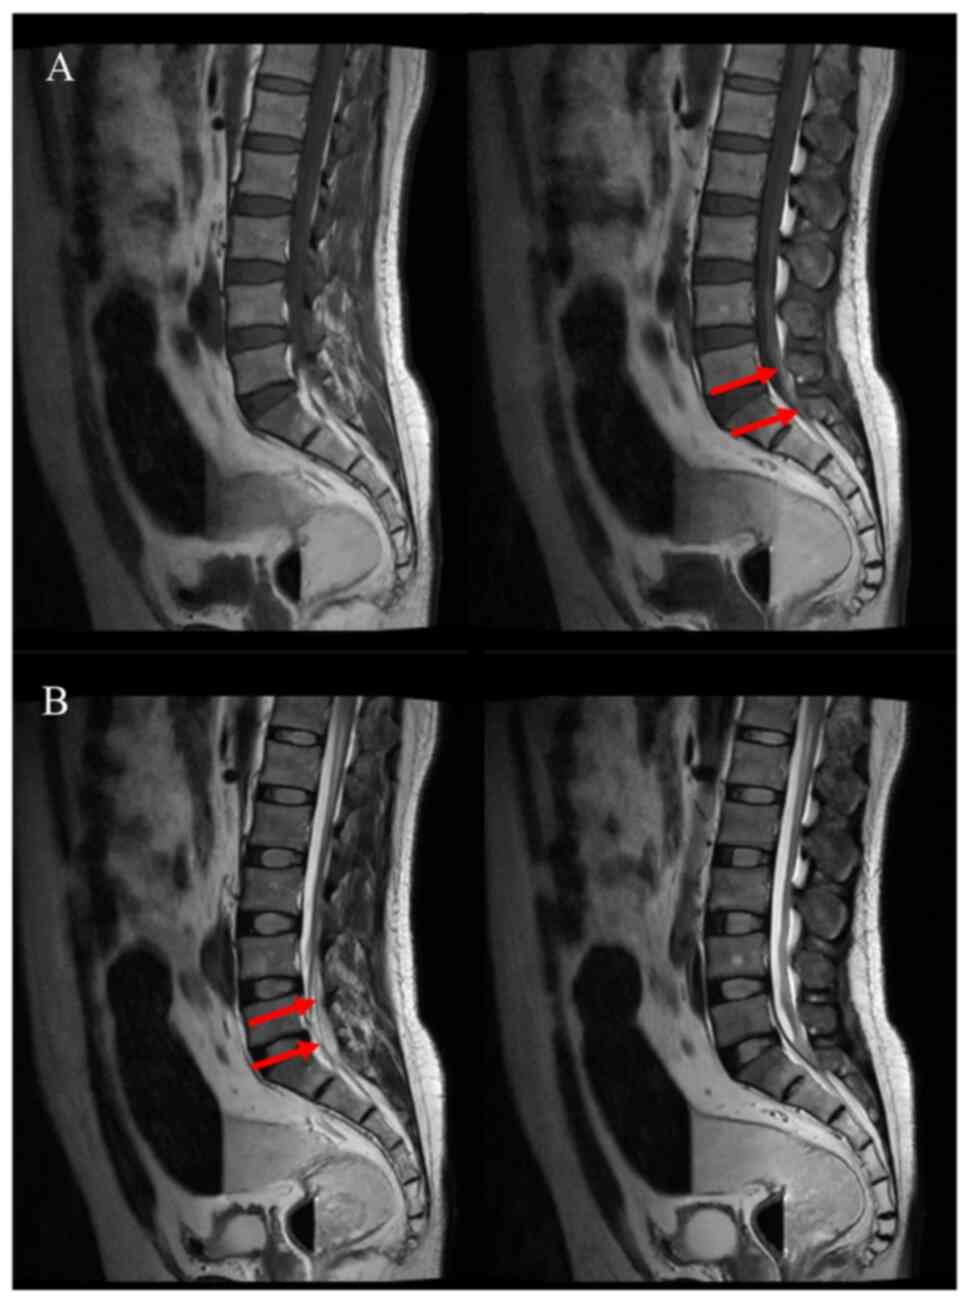

After the operation, the patient was transferred to the intensive care unit with tracheal intubation. Following regaining of consciousness and stability of vital signs, the tracheal intubation was removed and the patient was transferred to the general ward on the second day after the operation. The patient was awake and his GCS score was 15 points. The muscle strength assessment was using Lovett's grading approach (8), the muscle strength of both upper limbs of the patient was normal, while the muscle strength of both lower limbs was grade 0, but leg sensation of the patient was normal. No new hemorrhage was detected in the re-examined head CT area on the first day after surgery (Fig. 3). To determine whether the patient's paraplegia was related to the thoracolumbosacral spine, the patient underwent thoracic spine (5 days after the surgery) and lumbosacral spine (4 days after the surgery) magnetic resonance imaging (MRI) examination and lower extremity venous ultrasonography (10 days after the surgery). The thoracic spine MRI scan indicated mild degeneration of the thoracic spine, mild kyphosis of the T4/5 and T5/6 intervertebral discs and mild right kyphosis of the T7/8 intervertebral disc. T3 and T10 vertebral hemangiomas were suspected, as indicated by the red arrow in Fig. 4. The lumbosacral spine MRI scan revealed slight hematoma in the subarachnoid space below the L2 level, as indicated by the red arrow in Fig. 5.

Figure 4

Weighted MRI of the patient's thoracic spine 5 days after the surgery. (A) T1-weighted and (B) T2-weighted MRI images. T3 and T10 vertebral hemangiomas were suspected, as indicated by the red arrow. MRI, magnetic resonance imaging.

Figure 5

Weighted MRI of the patient's lumbosacral spine 4 days after the surgery. (A) T1-weighted and (B) T2-weighted MRI images. The lumbosacral spine MRI scan indicated a slight hematoma in the subarachnoid space below the L2 level, as indicated by the red arrow. MRI, magnetic resonance imaging.